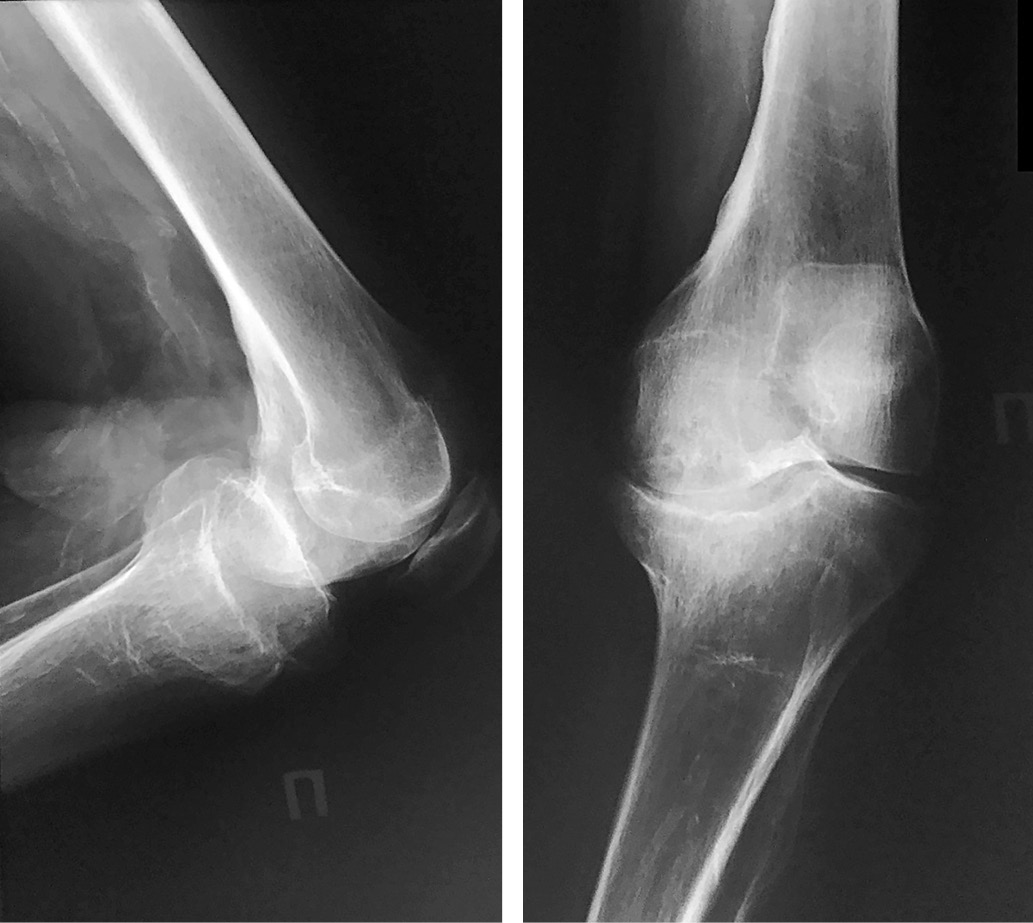

С 2009 г. на рентгенограмме коленных суставов отмечался остеопороз, параоссальные обызвествления, справа – деформация суставных поверхностей, расплющивание мыщелков большеберцовой кости с выраженной перестройкой костной структуры, асимметрия формы и размеров коленных суставов (правосторонний артрозоартрит с грубой деформацией суставных поверхностей, диабетическая артропатия) (рис. 2).

Рис. 2. Рентгенограмма левого коленного сустава, выполненная в боковой проекции, 2009 г.

В 1996 г. в остеоартропатический процесс был вовлечен локтевой сустав слева (рис. 1).

Рис. 1. Рентгенограммы левого коленного сустава, 1996 г.